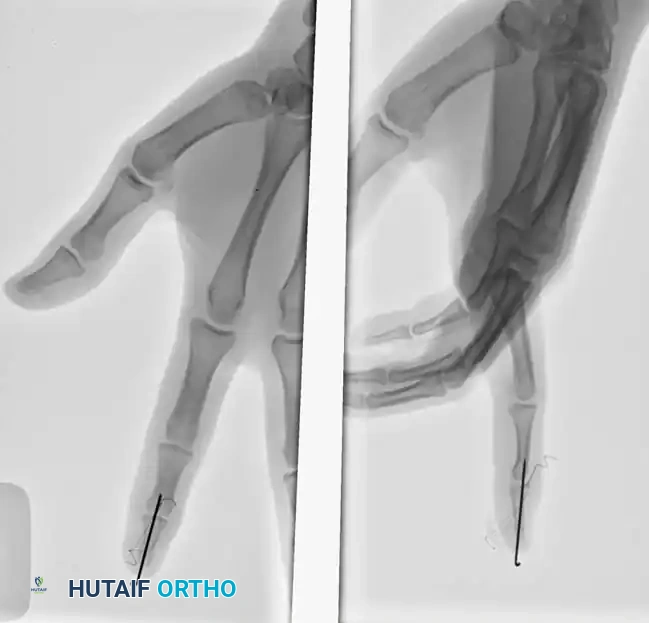

3. Fragment Fixation (Pull-out Suture): If the dorsal fracture fragment cannot be maintained in rigid apposition to the major diaphyseal fragment, a pull-out suture technique is required. Pass a non-absorbable suture (e.g., 4-0 Prolene) through the extensor tendon insertion on the fragment.

INTRAARTICULAR FRACTURES Surgical Diagram

1. Securing the Suture: Pass the two ends of the suture volarly through the distal phalanx, exiting the volar pulp. Tie the suture over a heavily padded external button to compress the fragment into place.

Surgical Pitfall: Insufficient padding beneath the volar button will cause rapid ischemic necrosis of the digital pulp. Always use a sterile felt pad or a piece of foam under the button, and avoid excessive tension when tying the suture.